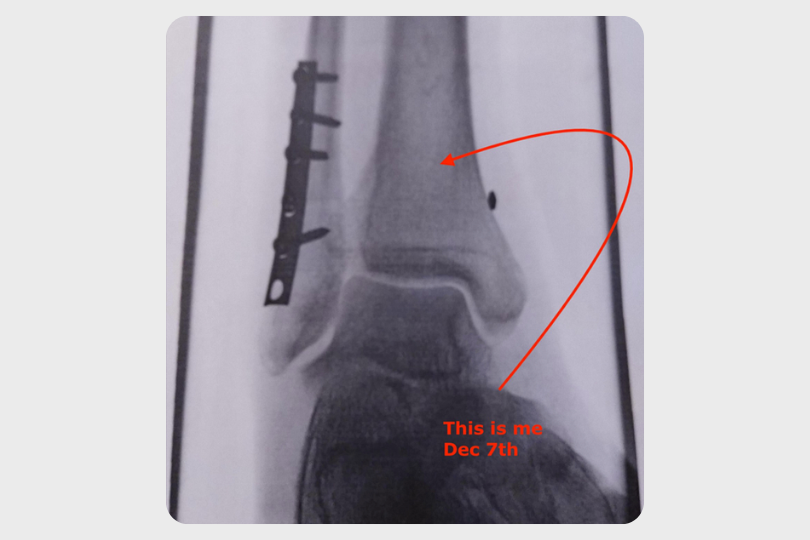

Data-Driven Recovery

Sean Ross-Ross discusses his rehab from a high syndesmotic ankle fracture and how Plantiga supported his journey back to health.